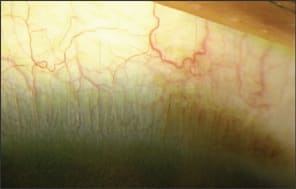

Pluripotent, undifferentiated stem cells are present in all selfrenewing body tissues and maintain a steady-state population of healthy cells. The stem cells of the corneal epithelium are situated at the limbus, nestled within the undulating folds of the Palisades of Vogt (Figure 1).

Figure 1. A small portion of the limbus: note the ridges and pigment characteristic of the Palisades of Vogt.

The limbus is a narrow annular transition zone that separates the anatomically contiguous, yet phenotypically different cells of the conjunctival and corneal epithelium. It has a distinct histological architecture. It differs from conjunctiva in that it is devoid of goblet cells, and unlike the optically clear corneal epithelium, it has Langerhan's cells, melanocytes, and underlying blood vessels.